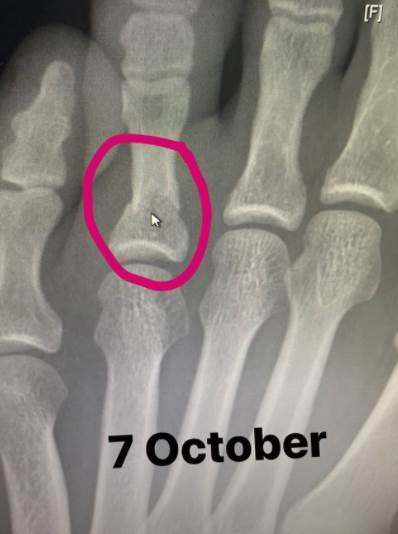

Habib je na svom Instagram "storiju" pokazao i rentgendski snimak slomljenog palca:

Na obe fotografije ispisan je datum – renten od 7. a otečeno stopalo od 8. oktobra. Meč je održan 24.

"Nakon svega što je taj dečko prošao u poslednje možemo biti srećni što smo imali priliku da ga gledamo večeras. Čuo sam da je pre tri nedelje slomio stopalo i to nikome nije rekao. Na stopalu ima slomljena dva prsta i jednu kost. On je jedno od najizdržljivijih ljudskih bića na planeti", ispričao je Vajt, koji je prvi otkrio novinarima o povredi.

Sada vidimo da je imao problema i 16 dana pre borbe…